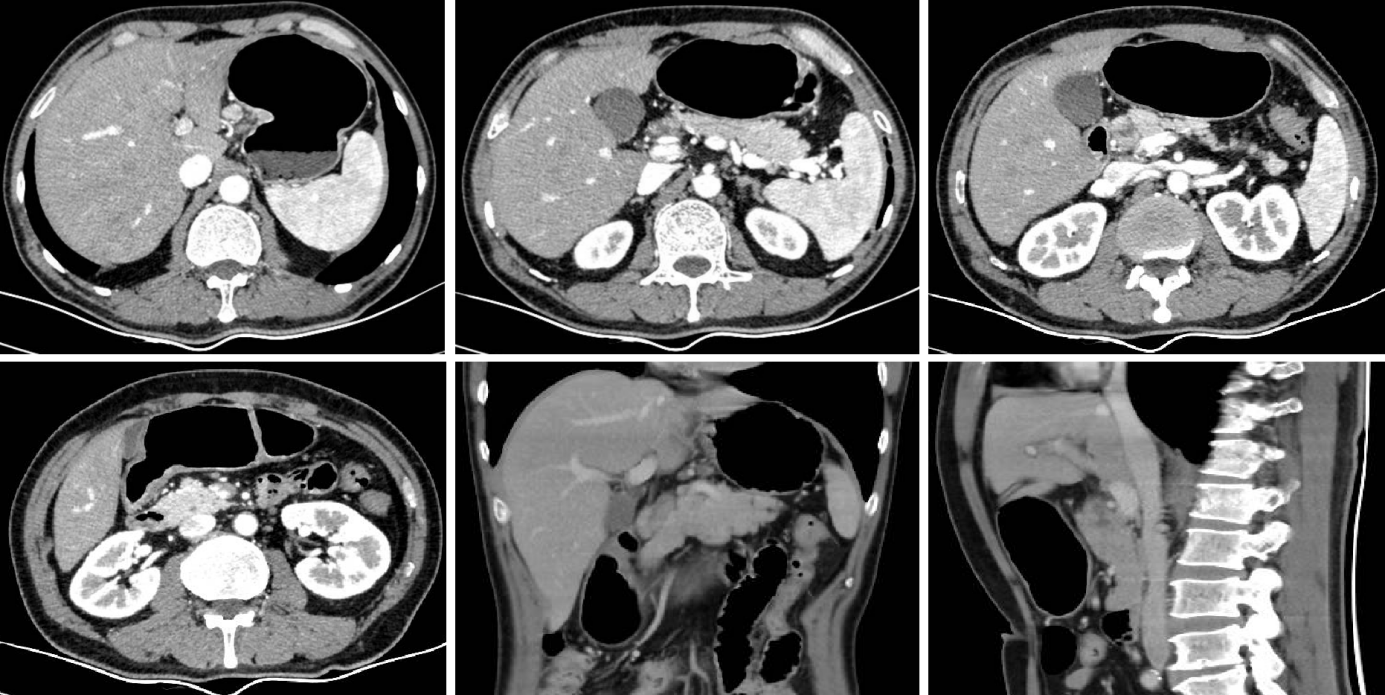

2023-12-15于当地医院复查腹盆CT:胃窦壁不均匀性增厚,呈中度略不均匀强化,肝胃间隙、肝门区及大网膜区见肿大淋巴结,大者最大截面约3.4*3.3cm,腹膜后可见稍大淋巴结。2023-12-16查肿瘤标志物:AFP 1403.1ng/ml, CEA 11.01ng/ml。2024-01-08患者继续当地医院行第4周期治疗,用药:奥沙利铂+卡培他滨+信迪利单抗。期间2024-01-06查肿瘤标志物:AFP 666.39ng/ml, CEA 7.72ng/ml。治疗后评效SD。

2024-03-12腹盆CT回报:对比2024-01-19腹盆CT:胃窦部胃壁增厚减轻,较厚处原约12mm,现约9mm,与正常胃壁分界不清,浆膜面模糊。No.1-3,7-8,9组多发淋巴结,部分增大,较大原约34*31mm,现约46*31mm,与胰腺分界欠清(图2)。临床疗效评价:综合考虑PD。

2024-04-12行第2周期行维迪西妥单抗+伦伐替尼+替雷利珠单抗治疗。2024-04-26、2024-05-03行第3周期行维迪西妥单抗+伦伐替尼+替雷利珠单抗治疗,过程中监测见患者AFP持续下降,2024-03-28为630.4ng/ml,2024-05-02为102.3ng/ml。期间于2024-04-24复查CT示:对比2024-03-12 腹盆部CT:胃窦部胃壁增厚大致同前,较厚仍约9mm,增强扫描强化明显。No.1-3,7-8,9组多发淋巴结部分缩小,较大原约46*31mm,现约25*22mm,与胰腺分界欠清。

2024-05-28再次复查CT示:对比2024-04-24腹盆部CT:胃窦部胃壁增厚大致同前,较厚仍约9mm,增强扫描强化明显。No.1-3,7-8,9组多发淋巴结部分缩小,较大原约25*22mm,现约14*13mm,与胰腺分界欠清(图3)。临床疗效评价:PR。